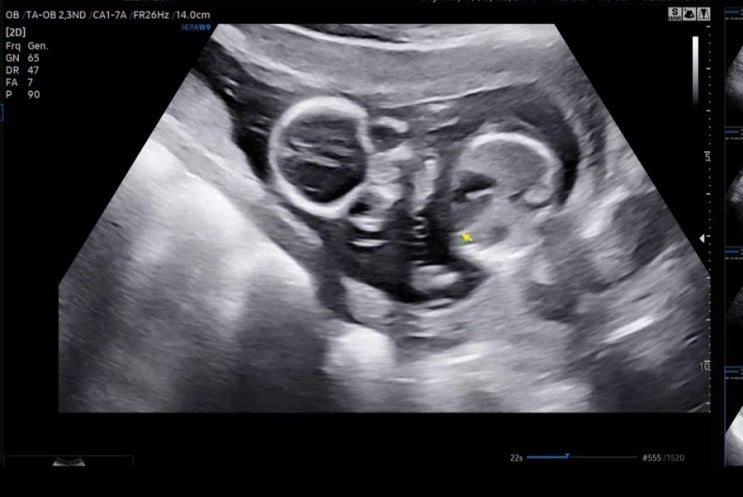

[젠또일기] 임신 25주 (아인병원 임당검사, 입체초음파, 임당 재검 통과, 랄츠 임신축하선물)

임신 25주, 임당 검사 임신 25주차의 빅 이벤트는 대망의 임당 검사 .. ! 푸꾸옥에서 망고만 팼기에 살짝 ...